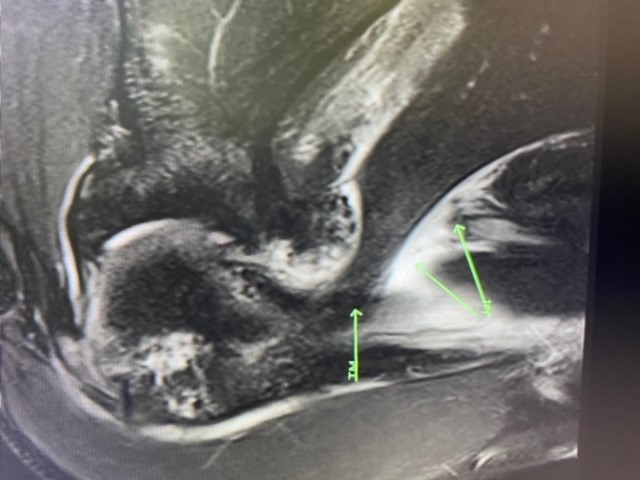

FEVER stress view position developed by Dr. Lund at SimonMed.

FEVER stress view developed by Dr. Lund at SimonMed with joint space widening.